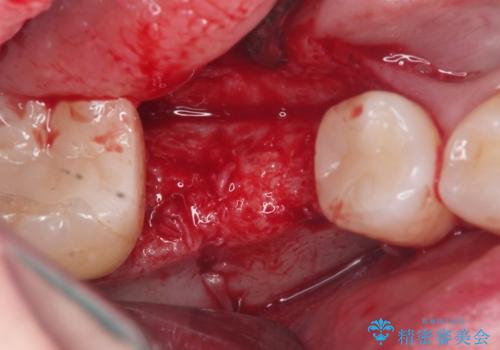

骨の増成を含むインプラント治療を計画します。

安定し、長く使用できるようなインプラント治療を実践するため、骨の増成をインプラント埋入と同時に行いました。